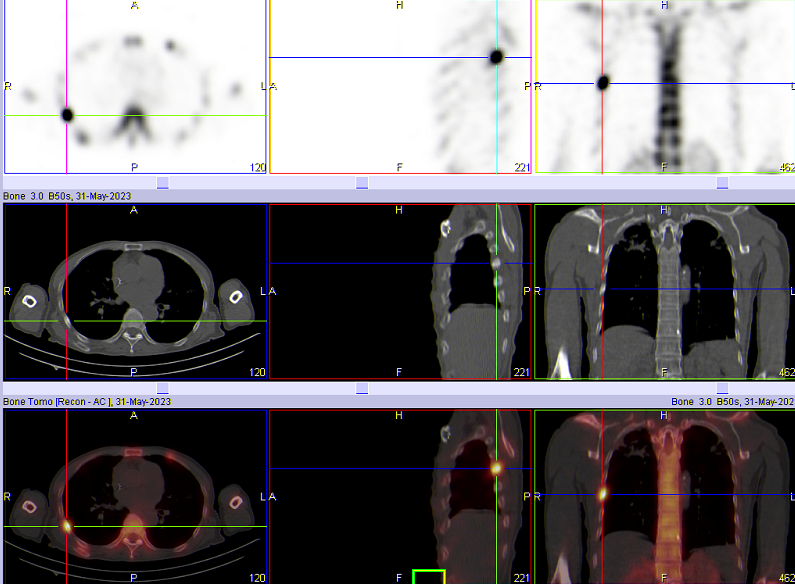

如图所示,胃恶性肿瘤患者,全身骨扫描显示:右侧第6腋肋放射性摄取增高,左侧第3-6前肋放射性摄取增高。进一步加做胸廓断层显像(SPECT/CT)后,影像显示右侧第6腋肋局部放射性摄取增高灶,肋骨骨密度增高,诊断为骨转移;左侧第3-6前肋放射性摄取增高,局部骨皮质皱褶,欠连续,诊断为陈旧性骨折。